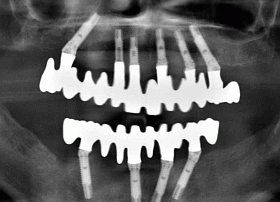

This X-ray shows the final result with All-on-6 (for the upper jaw) & All-on-4 (for the lower jaw) systems where 10 NOBEL BIOCARE – BRANEMARK dental implants were used. This treatment required 6 months healing period between initial placment of implants and fitting of final bridges.

In order to make All-on-6 & All-On-4 restorations successful, some Branemark implants are placed at an angle (see X-ray photo), requiring careful planning and placement of implants, which would in turn provide maximum strength to support final restorations to be screwed onto implants.